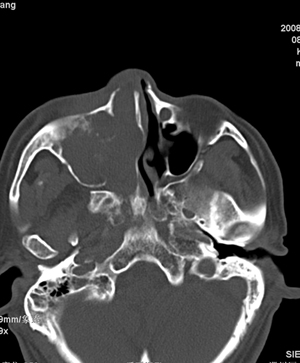

以下是引用影象小辈在2008-5-4 13:34:00的发言:[br]鼻腔及右侧上颌窦 筛窦内软组织密度影, 相邻鼻中隔、鼻甲及窦壁骨质破坏吸收,病灶延伸至鼻咽腔及右侧眼眶 多考虑为1.乳头状瘤 2.息肉 建议增强及活检

以下是引用peijunlong在2008-5-4 13:35:00的发言:[br]考虑右侧鼻腔内翻性乳头状瘤[br]好发:中老年人。[br]ct:1:一侧鼻腔内肿块经扩大的自然孔道长入鼻窦,是其顺自然孔道蔓延的特点[br] 2:鼻腔,鼻窦扩大,窦壁压迫性骨质破坏。[br] 3:广泛生长的肿瘤可侵犯邻近结构,如眼眶、翼腭窝和颅内。

以下是引用不学无术在2008-5-4 20:43:00的发言:[br]病人已在齐鲁医院穿刺活检病理结果:中分化鳞癌。